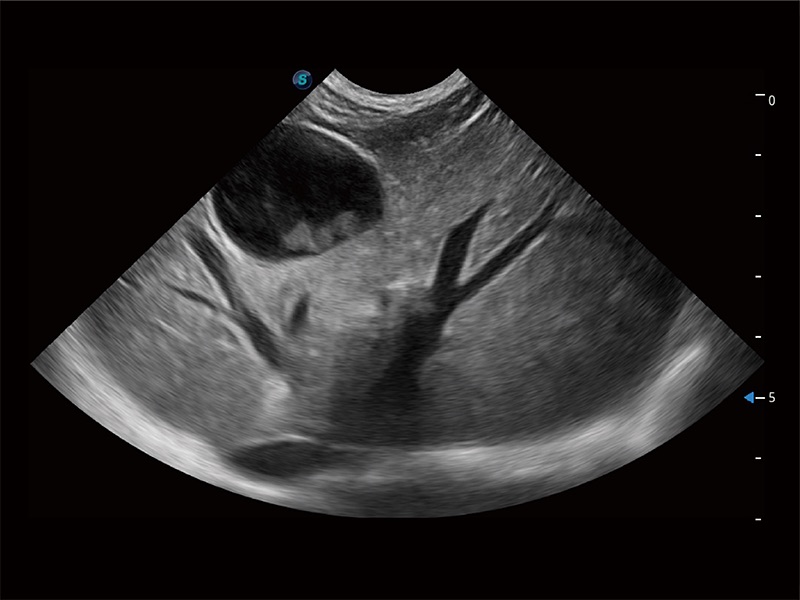

高性能和先进的临床应用工具可以为动物医生提供临床信心。ProPet 80 搭载了先进的腹部和浅表应用工具,帮助医生在日常临床实践中发挥前所未有的作用。

极大提升超低速微细血流的检出能力,同时更精准地滤除软组织和超声信号,为兽用医生提供以往无法通过常规血流获得的疾病诊断信息。

在传统二维血流成像的基础上,呈现血流的立体感,具有动感的生命力之美。即便是微小的血管也能轻松应对,提高了血流的视觉敏感性。